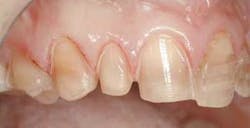

From this information, we are able to ascertain many things. First, after ruling out any periodontal disease and noting a comfortable and asymptomatic TMJ, we can turn our attention to the esthetic concerns. As you can see in figure 2, there are many things that can be improved. Let's go through this very methodically, using principles taught by the experts in the field, and see what we can improve.

With our patient, this evaluation reveals the centrals to be approximately 8.5 mm wide and 9.5 mm long. (Fig. 3) This would make the existing W/L ratio 89 percent. The Golden Proportion evaluation shows that the centrals appear too wide and we see too much of the canines.

Here we look at the dental midline as well as the facial midline. Also, is the smile canted to one side? What we found was that the dental midline is slightly off. When you look more closely, tooth #9 is slightly overlapping giving the appearance of the midline being off.

For the most visually pleasing effect, the teeth should have a slight mesial axial inclination. The observation of our patient's teeth reveals inclinations that do not follow this rule (Fig. 4 – black lines are desired; yellow lines existing).